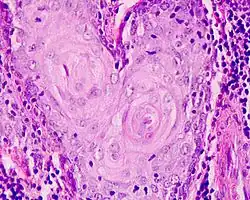

Najczęstszym typem nowotworu złośliwego krtani jest rak płaskonabłonkowy (90%).

- rak płaskonabłonkowy (carcinoma planoepitheliale) około 95% przypadków